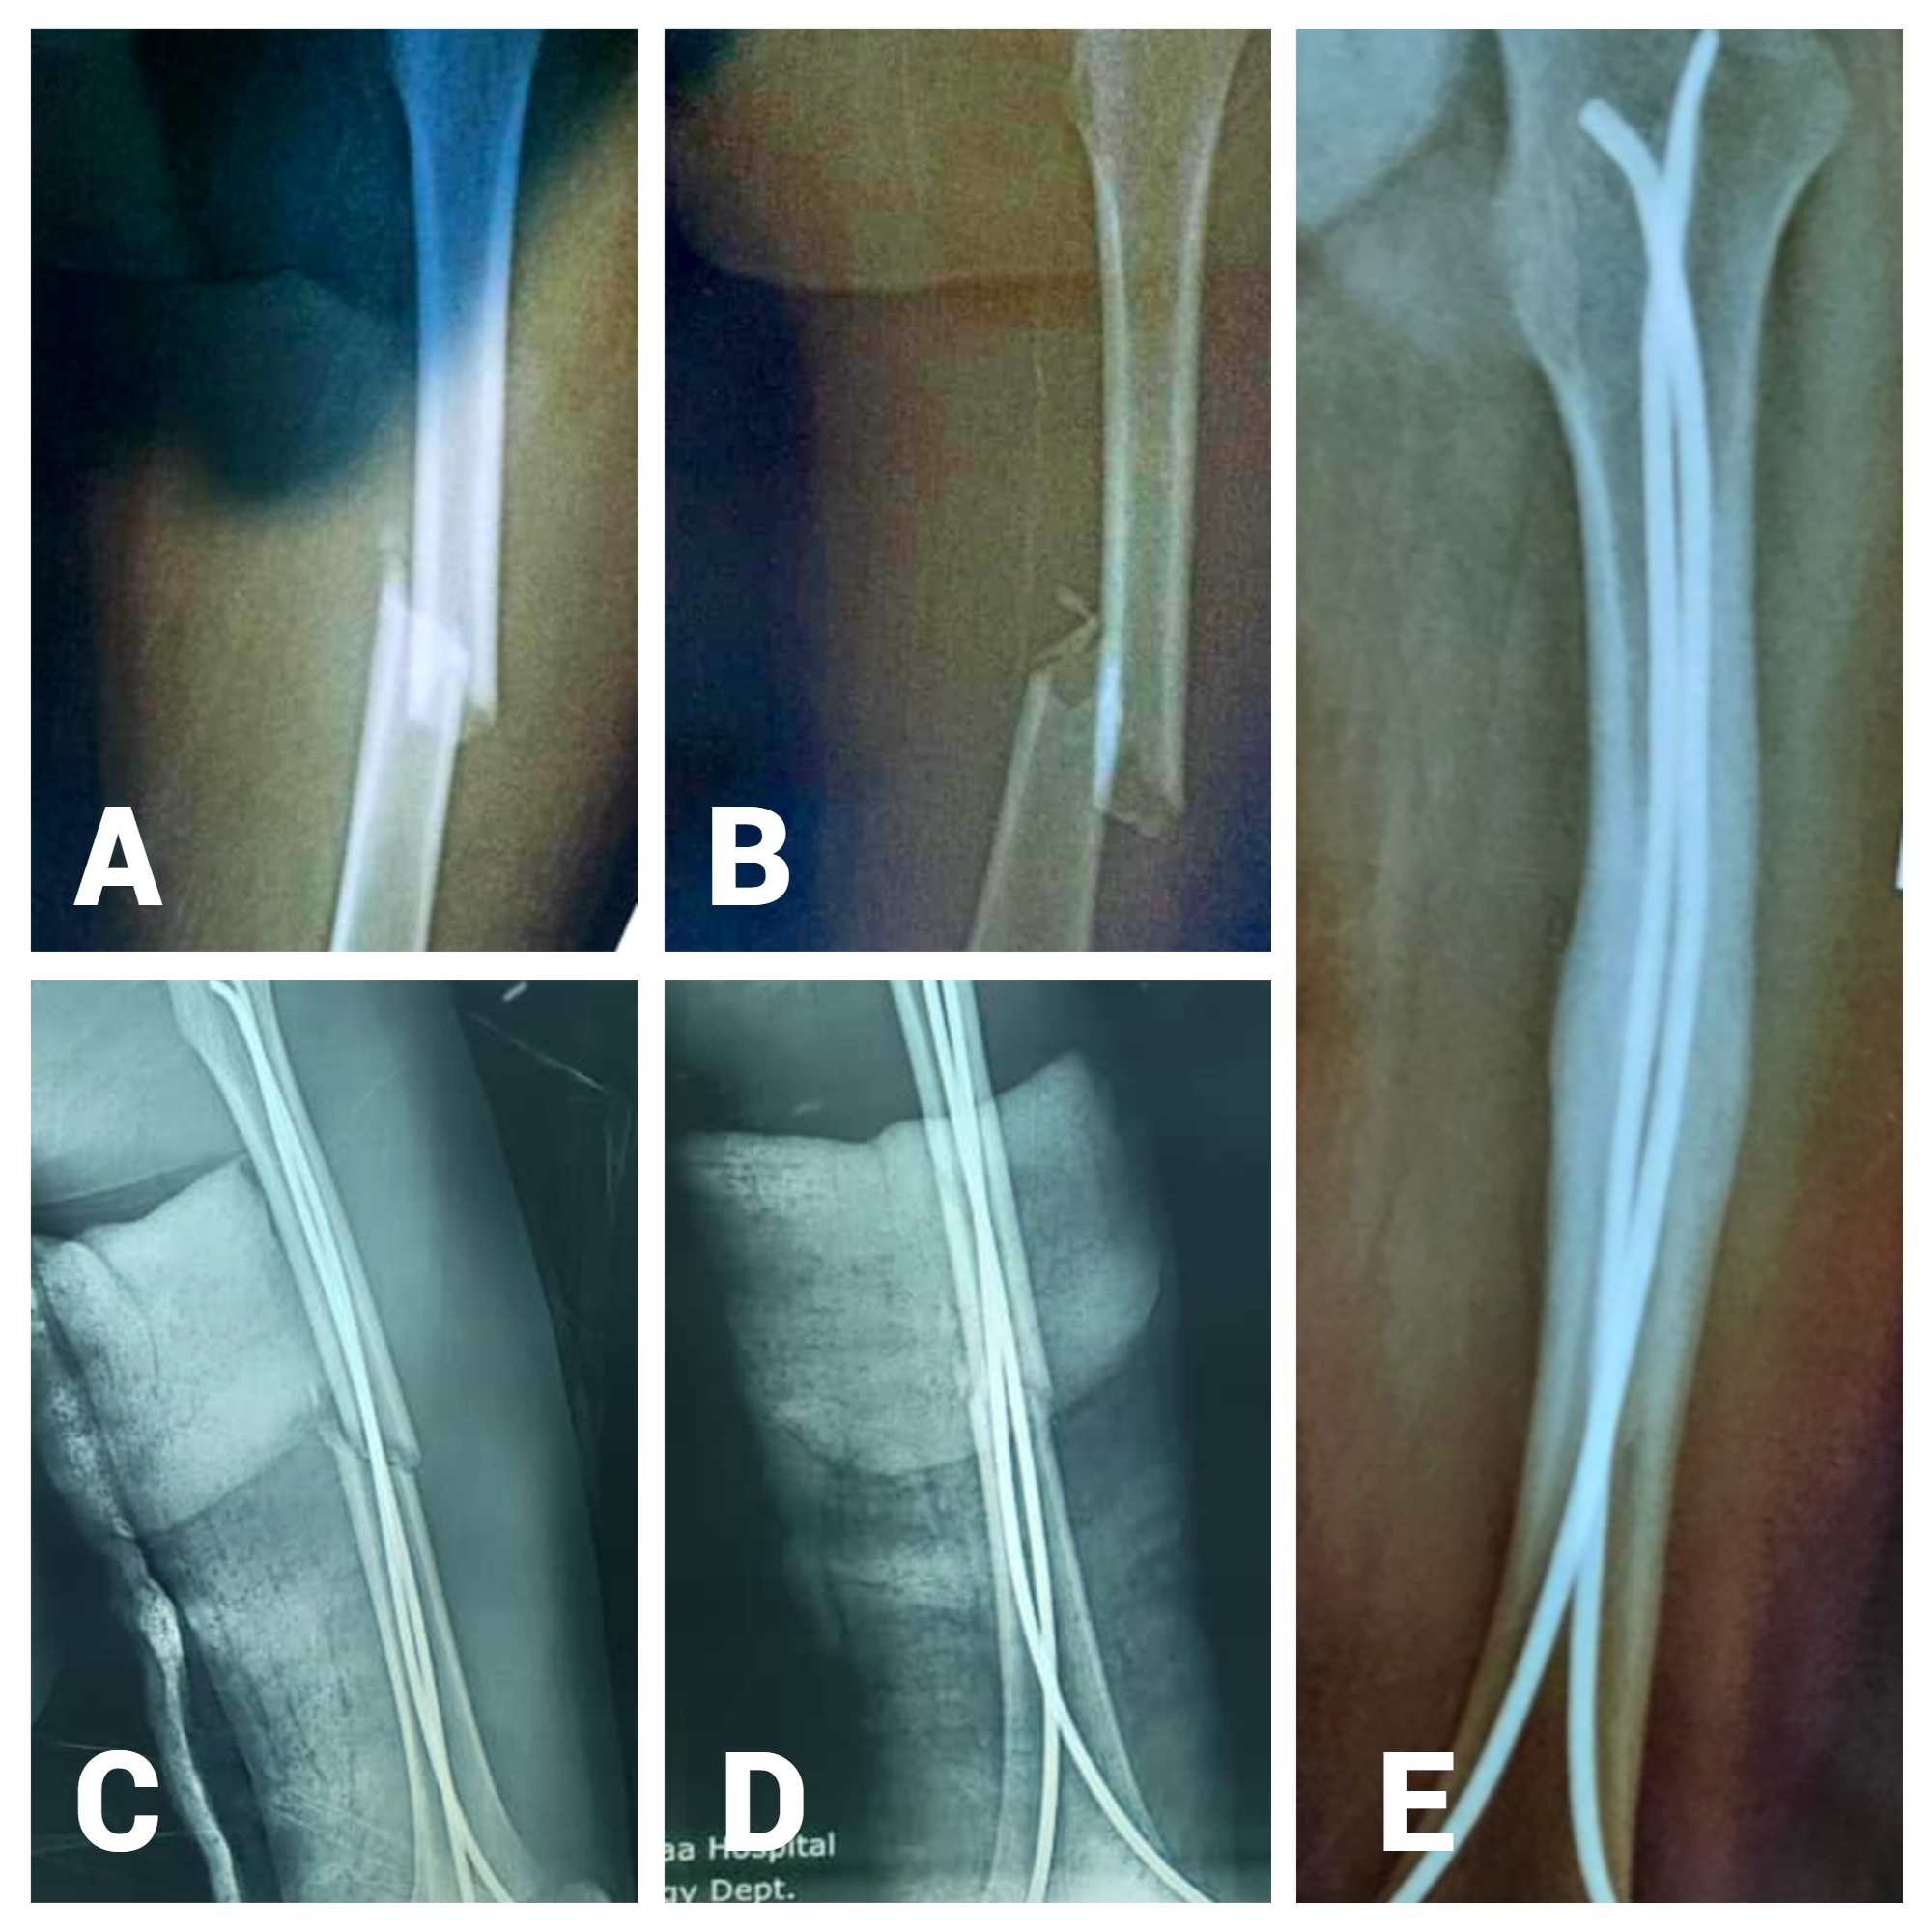

Functional Outcome of Femoral Fracture in Children Treated with Titanium Elastic Nailing System (TENS): A Prospective Study in Sana'a, Yemen

Dr. Abdulla Al-Moaish, Dr. Mohammed Hutaif, Dr. Mosleh Soliaman, Dr. Ali Mustafa Alhamzi, Dr.Hussam Abdulla AL-Durafi, Dr. Haitham Mohammed Jowah (Author)

227-231